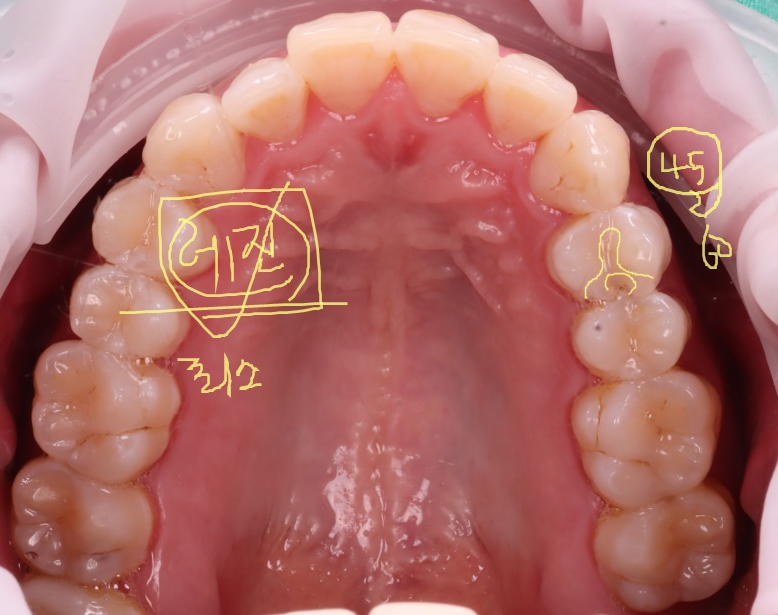

오늘 소개해 드릴 분은 40세 남성분으로 3년 전에 다른 치과에서 레진으로 치료했던 곳이 한 달 전쯤 깨지면서 떨어졌다고 하셨어요.

내원 당시 치아는 겉보기엔 멀쩡했지만 기존 레진이 떨어져 그 아래로 세균이 침투한 흔적이 있었어요.

촬영일 : 251020

이를 2차 충치라고 부르는데 적절히 치료되지 못한 경우에 접착이 깨지고 그 틈으로 세균이 침투해서 다시 충치가 생길 수 있어요.

생각보다 파절 부위가 커서 걱정이 됐는데요.

기존 재료를 제거한 뒤 확인해 보니 다행히 신경까지는 진행되지 않아서 크라운으로 덮지 않고 레진으로 충분히 복원 가능한 상태라 판단이 들었어요.